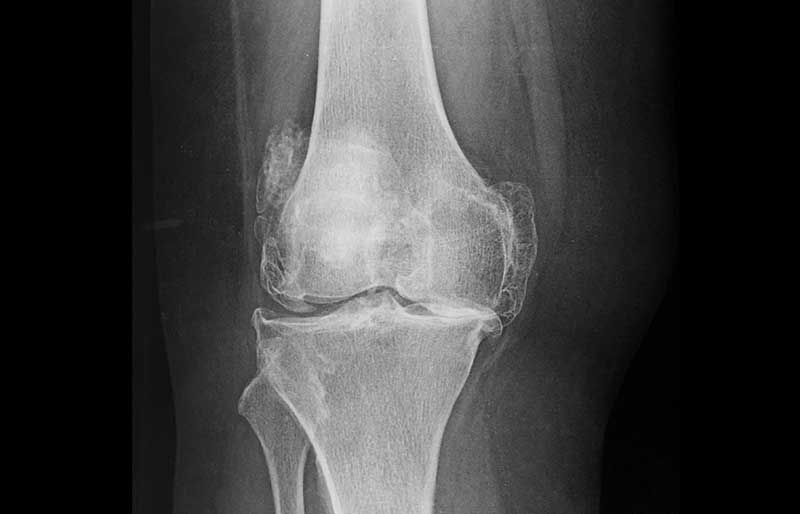

Kerusakan dan penipisan tulang rawan memicu terjadinya proses peradangan sendi (melalui terbentuknya beberapa zat kimia tertentu di dalam sendi), sehingga sendi terasa nyeri dan kadang-kadang membengkak. Jika penipisan semakin berat sehingga tulang rawan hilang sama sekali, maka ujung tulang pembentuk sendi saling bergesekan secara langsung sehingga menimbulkan rasa nyeri yang berat dan gangguan mekanis berupa bunyi “krek-krek” dan sendi menjadi kaku.

Pada stadium awal, keluhan penderita osteoartritis berupa nyeri dan kaku sendi setelah lama tidak bergerak; sebagai contoh, lutut terasa sakit dan kaku saat bangun tidur, saat berdiri dari posisi duduk atau saat turun dari mobil, atau saat berjongkok. Lutut juga terasa sakit jika digunakan naik atau turun tangga. Pada stadium yang lebih berat, lutut terasa sakit saat dipakai berjalan, terutama jika berjalan jauh. Sering terdengar bunyi “krek- krek” saat sendi digerakkan.